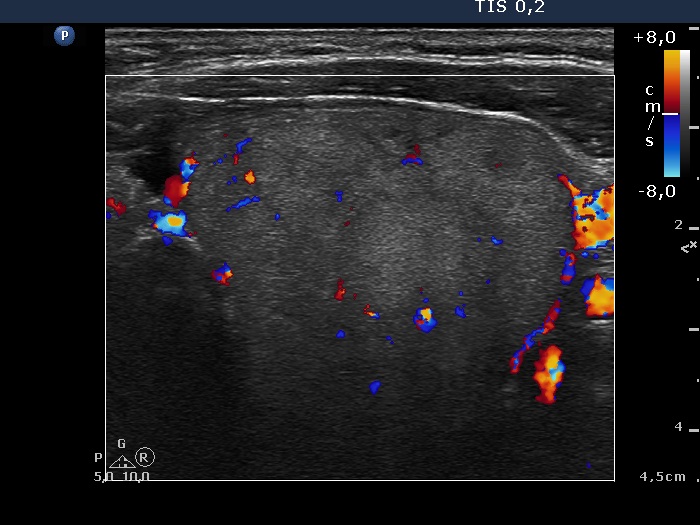

Left lobe, transverse scan, color Doppler view.